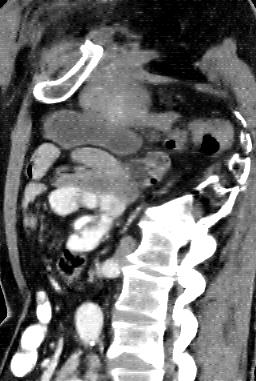

Due to the constraints of the imaging device and high cost in operation time, computer tomography (CT) scans are usually acquired with low intra-slice resolution. Improving the intra-slice resolution is beneficial to the disease diagnosis for both human experts and computer-aided systems. To this end, this paper builds a novel medical slice synthesis to increase the between-slice resolution. Considering that the ground-truth intermediate medical slices are always absent in clinical practice, we introduce the incremental cross-view mutual distillation strategy to accomplish this task in the self-supervised learning manner. Specifically, we model this problem from three different views: slice-wise interpolation from axial view and pixel-wise interpolation from coronal and sagittal views. Under this circumstance, the models learned from different views can distill valuable knowledge to guide the learning processes of each other. We can repeat this process to make the models synthesize intermediate slice data with increasing inter-slice resolution. To demonstrate the effectiveness of the proposed approach, we conduct comprehensive experiments on a large-scale CT dataset. Quantitative and qualitative comparison results show that our method outperforms state-of-the-art algorithms by clear margins.